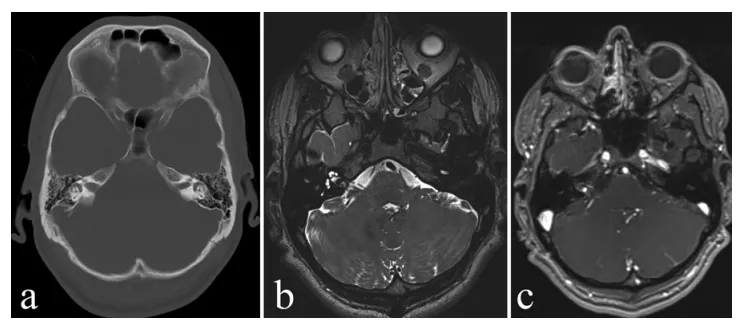

图1. 术前影像学检查结果:(a) CT图像显示右侧内听道呈现扩大改变。(b) MRI图像清晰显示内听道内的不典型病变。(c) 增强MRI图像显示病灶中心区域存在钆增强表现。

计算机断层扫描除显示右侧内听道扩大外,其余检查结果未见明显异常。计算机断层扫描血管造影未见血管异常。磁共振成像检查未发现静脉窦血栓形成、脑炎或脑卒中迹象,但明确显示内听道内存在一处形态不寻常的病灶。神经内科、神经放射科与神经外科团队开展多学科会诊讨论,鉴于患者神经症状呈进行性加重,最终决定将卡尔转诊至神经外科接受手术治疗。

22岁男性患者卡尔,临床表现为右侧听力丧失合并头痛症状,于当地医院接受激素输液等对症支持治疗,听力获得轻微改善。此阶段磁共振成像检查显示右侧内听道内存在不均匀钆增强病灶,临床初步怀疑为听神经瘤。